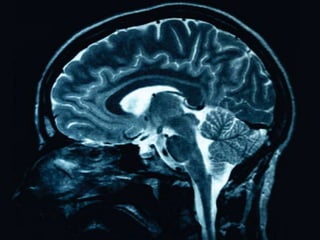

EEG measures brain activity using electrodes and records tracings to interpret physiological activity. CT scans and MRIs are used in psychiatry to investigate confusion, dementia, psychosis, catatonia, affective disorders, and personality changes after age 50 by providing anatomical and functional information. Psychological tests assess characteristics like intelligence, memory, attention, concentration, self-concept, perception, anxiety, depression, and coping patterns to aid in diagnosis.